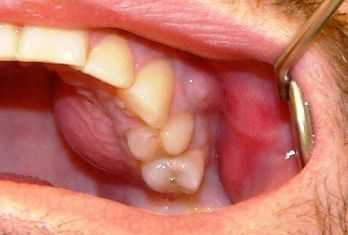

- Поражённый зуб постепенно расшатывается, и возникает синдром «клавиш» — соседние зубы тоже становятся подвижными.

Хроническая форма длится от нескольких месяцев до нескольких лет. Описанные выше симптомы то появляются, то стихают или даже полностью исчезают. При длительном течении болезни зубы становятся подвижными, челюсть утолщается и могут измениться контуры лица.

- подвижность одного или нескольких зубов;

Одним из самых первых симптомов, характерных для поражения нижней челюсти является понижение чувствительности нервных рецепторов подбородка и нижней губы. При этом если причиной заболевания является одонтогенный путь передачи, то наблюдается сильная боль в пораженном зубе.

При подостром течении остеомиелита состояние несколько улучшается, уменьшается выделение гнойного экссудата и симптоматика воспалительного процесса, но при этом сохраняется и усиливается подвижность зубов. Не стоит затягивать с походом к стоматологу, ведь только врач сможет правильно оценить степень поражения и назначить адекватную терапию.